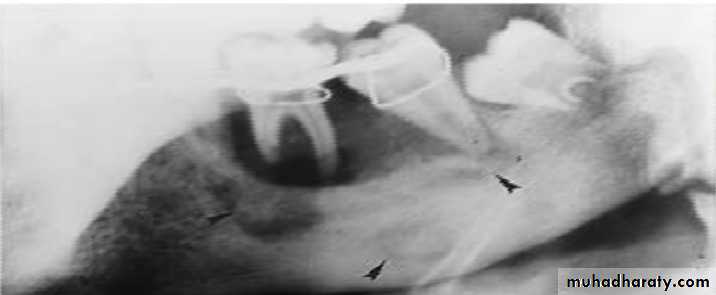

• After sufficient bone resorption irregular, mot- eaten areas of radiolucency may appear.

• RADIOGRAPHIC FEATURES

• May be normal in early stages of disease . Do not appear until after at least 10 days.• Radiograph may demonstrate ill-defined radiolucency.

• Mandible is more prone than maxilla as vascular supply is readily compromised.• Cropped panoramic radiograph of suppurative osteomyelitis at the right side of mandible.